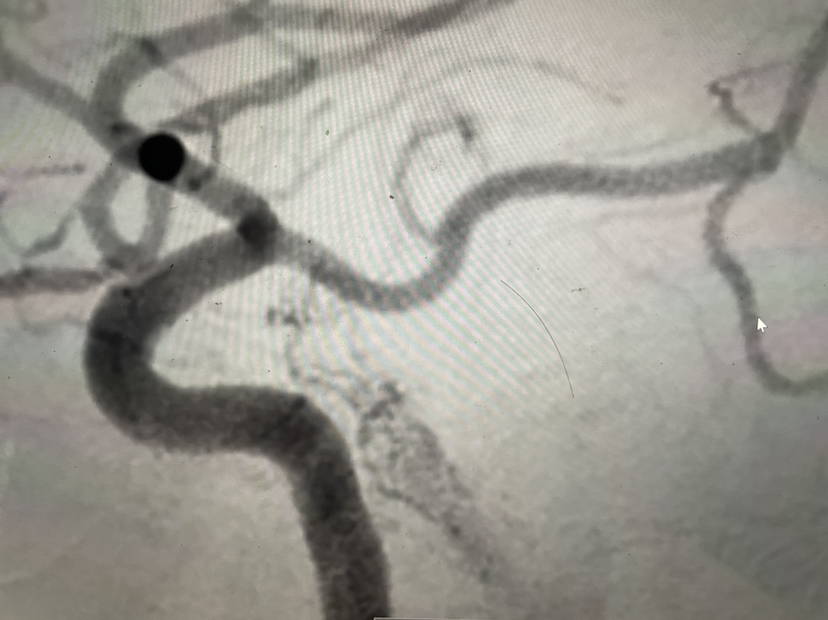

左侧海绵窦瘘向左侧岩下窦引流

左侧颈内动脉正位

左侧颈内动脉侧位,瘘口?

再艰难开通海绵间窦进去左侧海绵窦微导管造影

瘘口封堵满意,证实瘘口其实再在左侧海绵窦上,手术结束